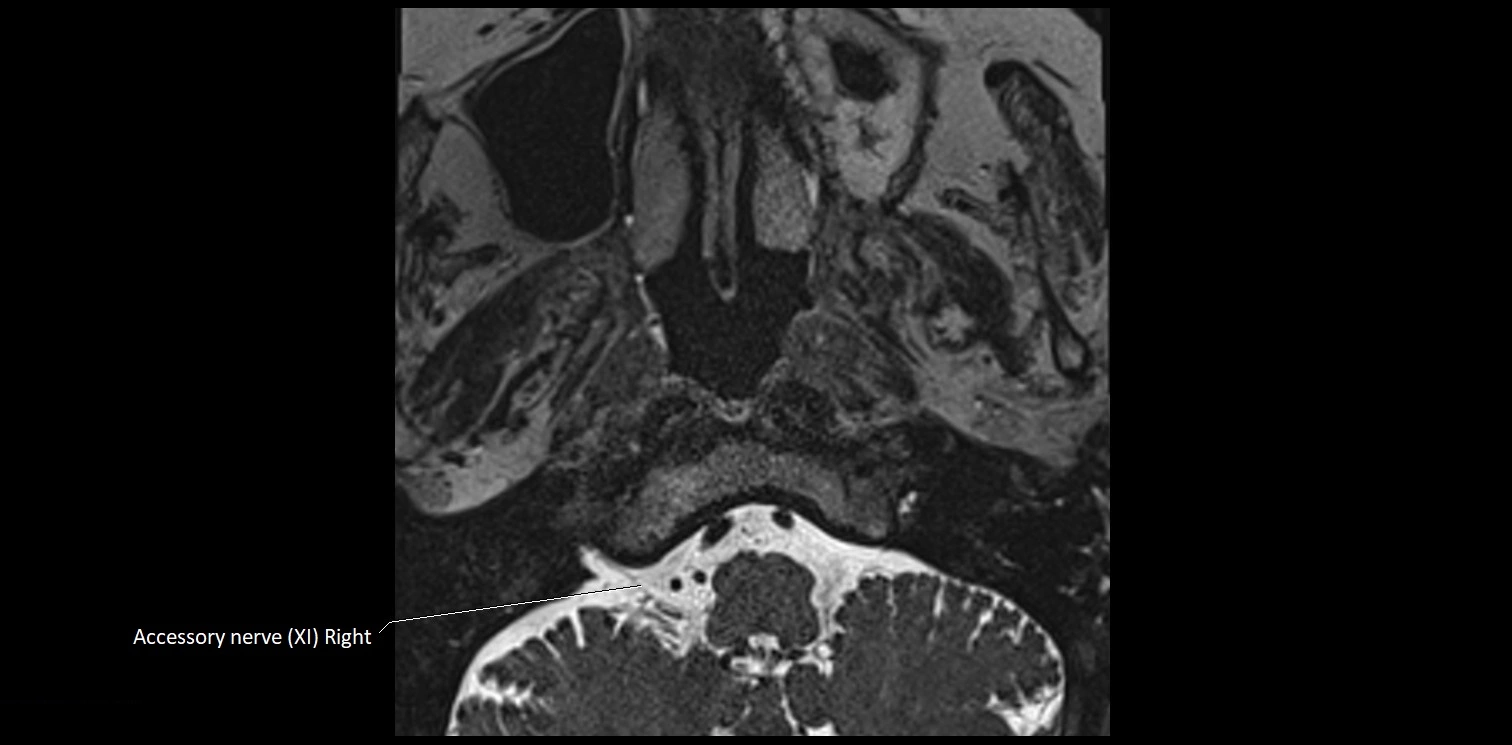

MRI Appearance

• The abducens nerve is a small, thin, linear structure

• Best visualized on high-resolution T2-weighted 3D MRI sequences (e.g., FIESTA or CISS)

• Seen as a hypointense (dark) line running from the brainstem at the pontomedullary junction, traversing the prepontine cistern, and entering Dorello’s canal under the petrosphenoidal ligament, then into the cavernous sinus, and finally the orbit

• May be challenging to visualize in standard MRI due to its small size

• Pathology may be inferred by absence, displacement, or enhancement of the nerve